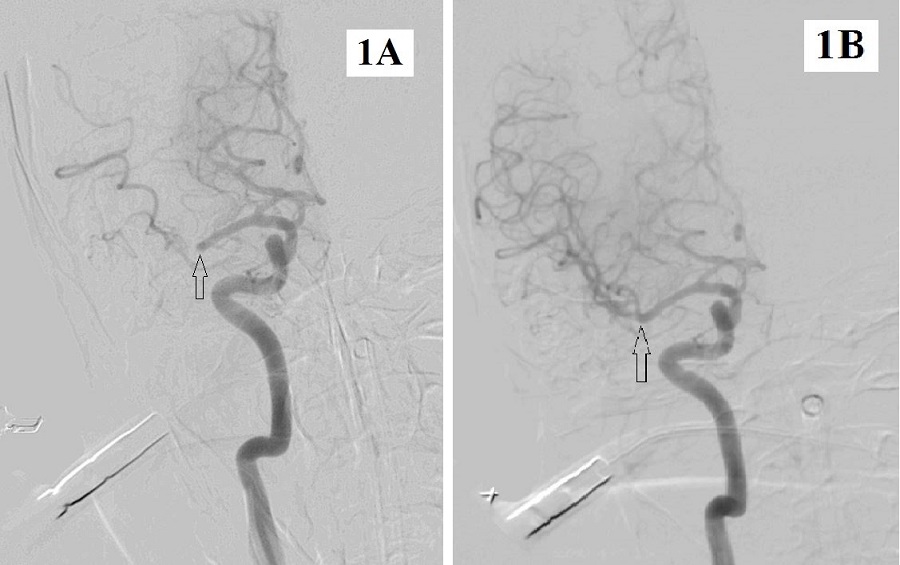

Hình 1A: Tắc đoạn cuối M1 động mạch não giữa phải;

Hình 1B: Tái thông hoàn toàn động mạch não giữa phải sau can thiệp lấy huyết khối bằng dụng cụ cơ học;